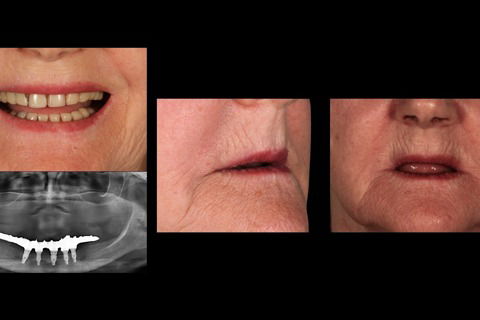

Suporte labial

Foto 16 Suporte labial